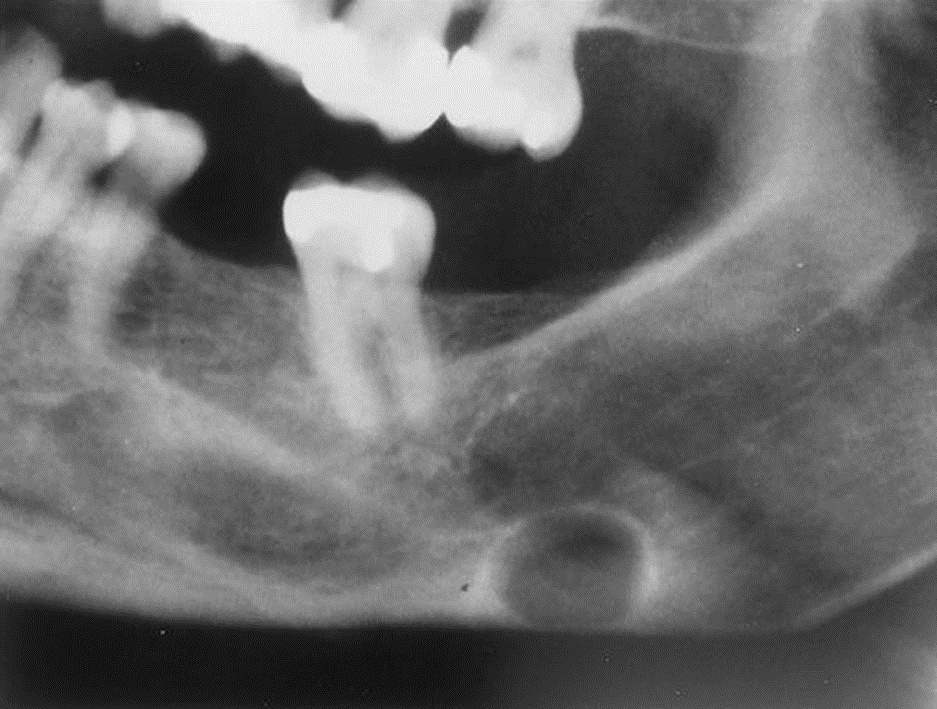

4. This 72-year-old woman presented with loose 20-yearold dentures and slight intermittent pain under the lower denture. She stated she had her teeth extracted because of severe untreated caries and abscessed teeth. The radiolucent lesion was detected on a radiograph of the painful area.

What is your diagnostic impression?